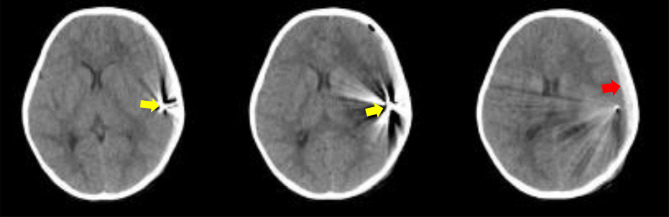

Traumatic brain injury (TBI) in the pediatric population is a major cause of morbidity and mortality. Between various etiologies of TBI, gunshot wounds occupy a unique characteristic and apprehensive place. We report a clinical case of a TBI due to a gunshot wound in Indonesia. A 4-year-old girl complained of a painful head and vomiting after sustaining a gunshot wound to the head. The patient was presented with a pediatric Glasgow Coma Scale (pGCS) score of E3V4M5 and was hemodynamically stable Multislice computerized tomography (MSCT) revealed a bullet lodged in the left temporal lobe, a subdural hematoma in the left frontoparietal-temporooccipital, an intracranial hemorrhage in the left temporoparietal region, and a midline shift to the right by 0.7 cm. The patient underwent craniotomy for subdural hematoma evacuation and bullet evacuation. Stable hemodynamics and brain relaxation conditions were achieved during surgery. Postoperative recovery in the pediatric intensive care unit (PICU) was uneventful, and the patient was discharged with improved neurological status (pGCS E4V5M6) without complications. The case highlights the successful management of a pediatric patient with traumatic brain injury due to a gunshot wound through a multidisciplinary and tailored approach focusing on hemodynamic stability, intracranial pressure management, early posttraumatic seizure, and infection prophylaxis to ensure a positive outcome. Given the scarcity of reported cases in low- and middle-income settings, this report provides valuable insights into the optimal management of pediatric gunshot-related TBIs.